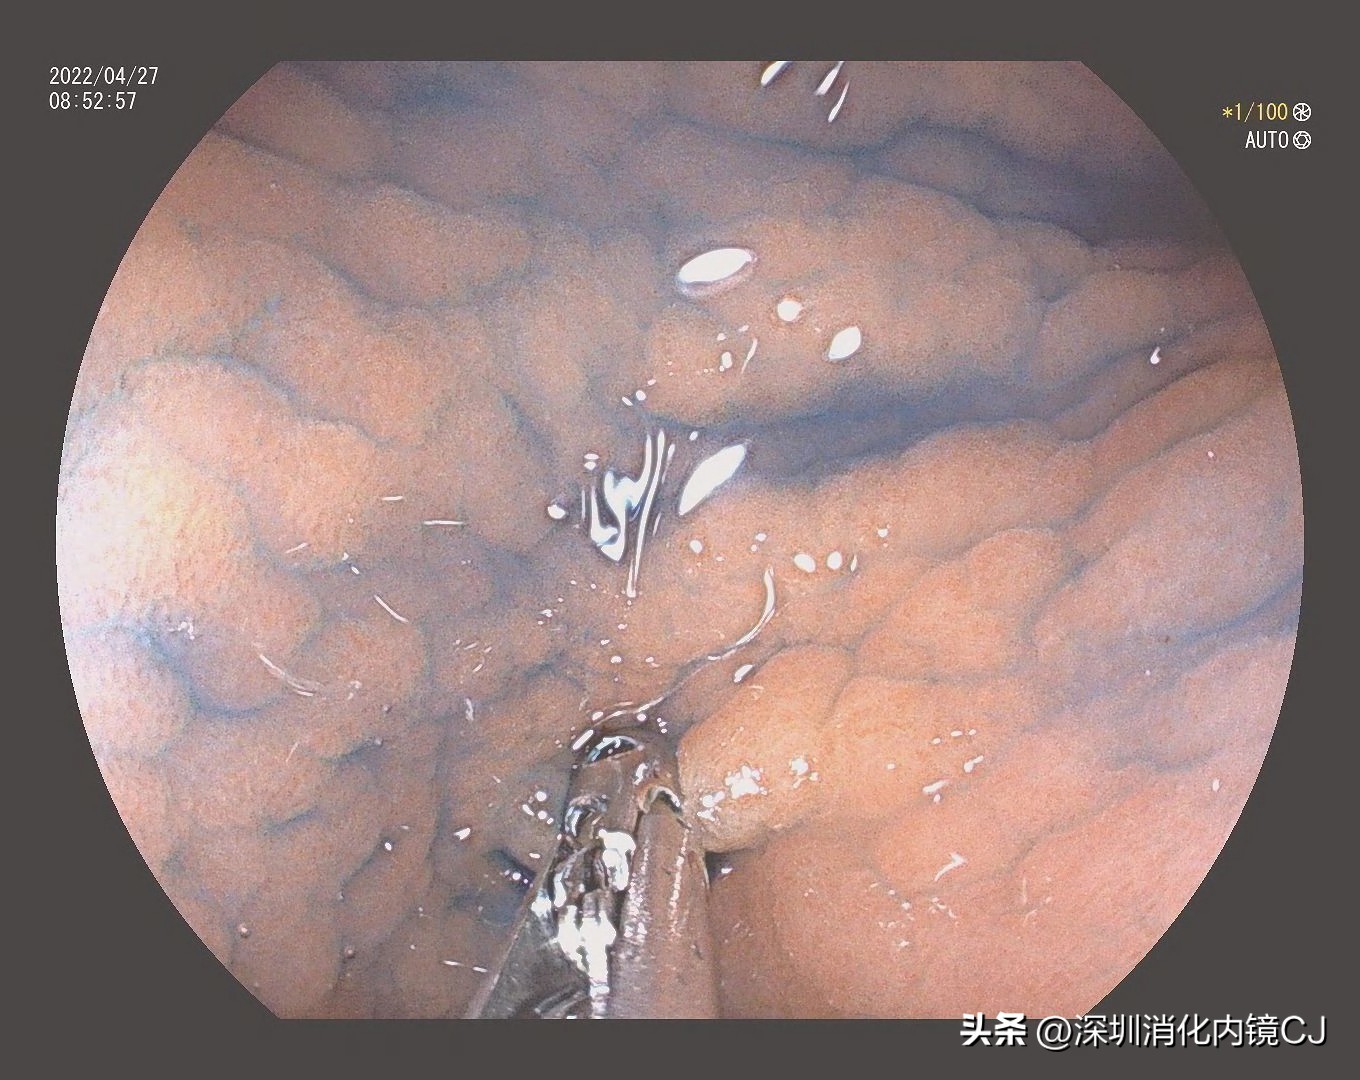

白光不明显

靛胭紫染色后鸡皮样表现明显

活检